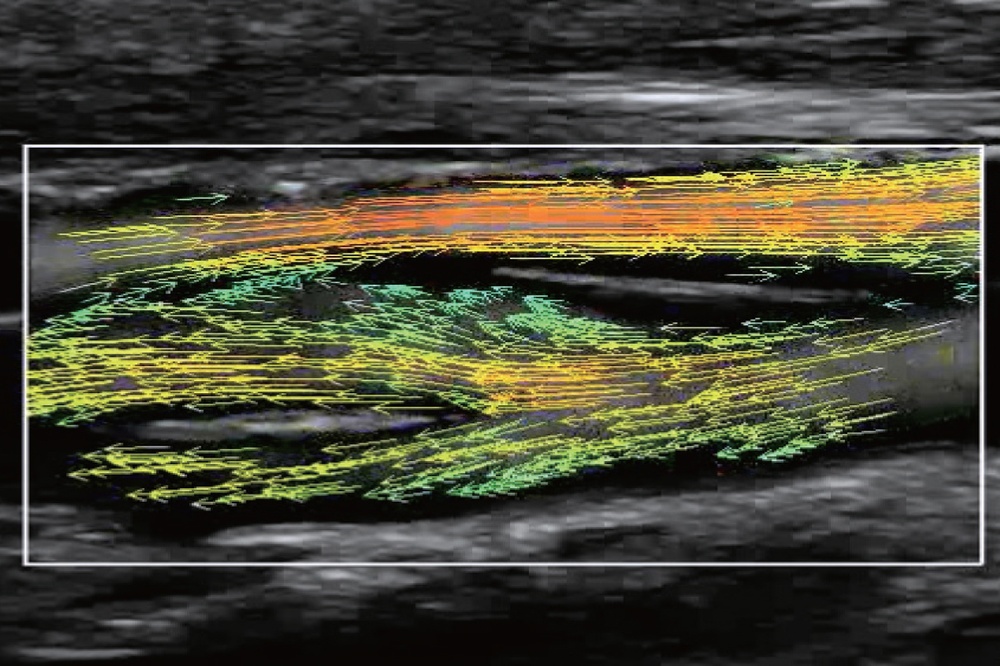

На изображениях, приведенных ниже показаны примеры из клинической практики врачей ультразвуковой диагностики, полученные в процессе апробирования прибора Mindray Resona 7. Приводится наглядные примеры сравнения традиционного режима ЦДК и режима V Flow (Vector Flow).

Изображен ламинарный поток сонной артерии. В режиме ЦДК отсутствует информация о профиле ламинарного потока. Режим V Flow визуализирует не только скоростные характеристики с помощью цветных стрелок, но и предоставляет данные о профиле ламинарного потока (быстрый поток в центре и медленный вблизи стенок сосуда).

Изображена яремная вена и бифуркация сонной артерии. CAA, ICA и ECA показаны на одном изображении. В режиме ЦДК отсутствует подробная гемодинамика. В режиме V Flow отображаются данные о скорости и направлении движения частиц крови во всей зоны интереса, включая изменения характеристик кровотока в сонной артерии и яремной вене.